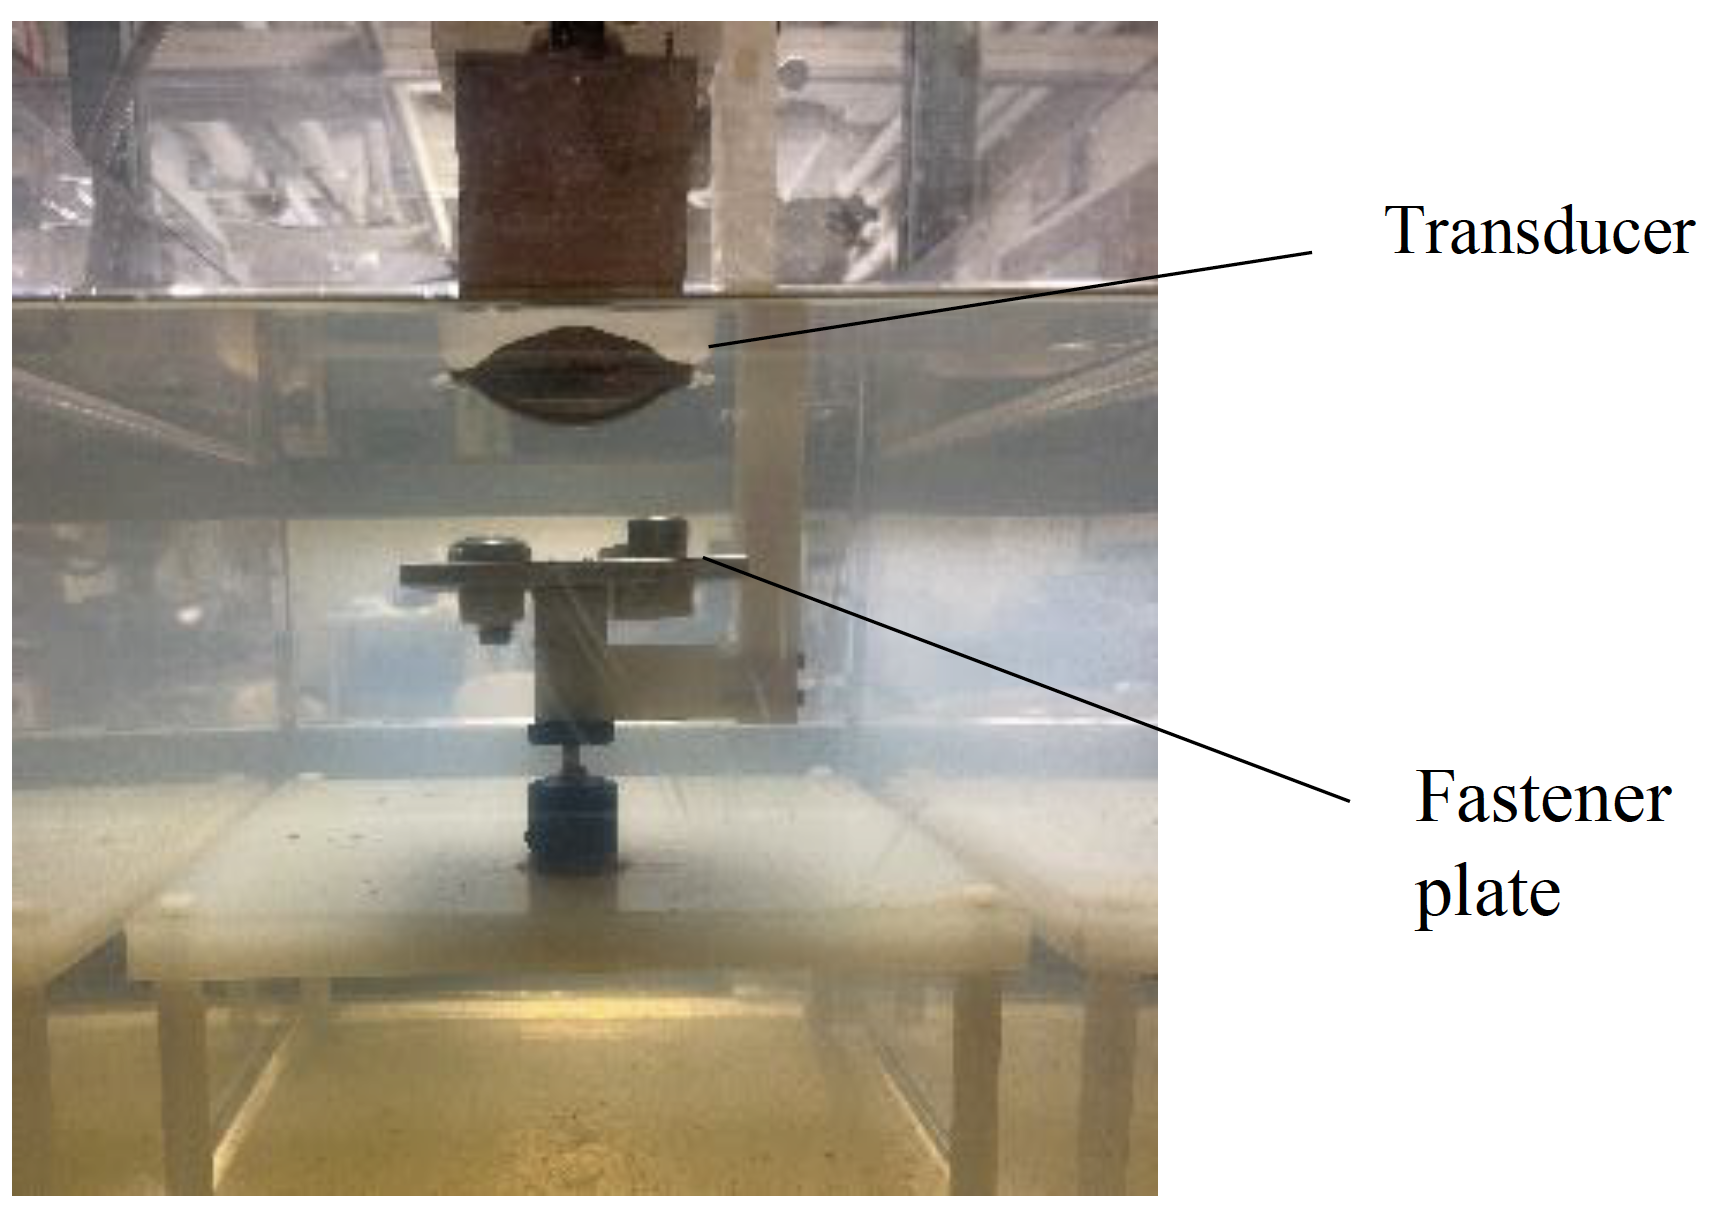

- Biologic Effects of Ultrasound in Healthcare Setting The instrument performing the emission of the sound waves and the recording of their bouncing back is referred to as the transducer and the medical practitioner generally gently presses the transducer against the skin of […]